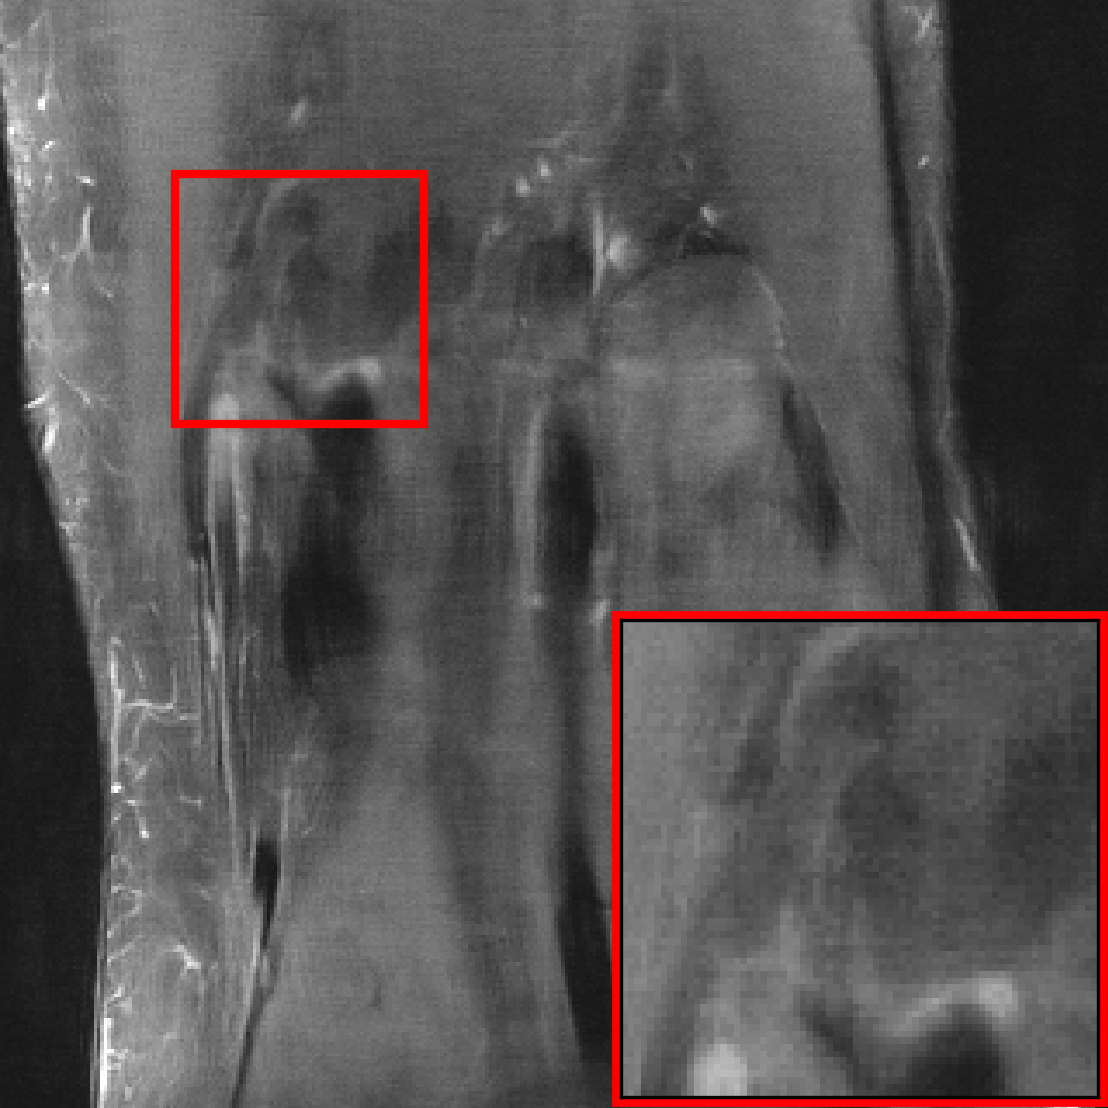

The results in Figure 8 show that for all architectures considered, the model trained on the collection of datasets, significantly outperforms the models trained on fastMRI data when evaluated on out-of-distribution data, without compromising performance on fastMRI data. For example, on the CC-359 sagittal view dataset, the VarNet trained on almost closes closes the distribution shift performance gap (i.e., the gap to the model trained on the out-of-distribution data). This robustness gain is illustrated in Figure 9 with examples images: the out-of-distribution images reconstructed by the model trained on the diverse dataset have higher quality and fewer artifacts.